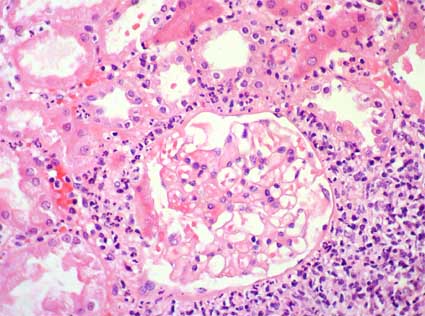

Cuando se presenta la enfermedad en su forma aguda, es común observar síntomas como edema intersticial, que es la acumulación anormal de líquido en el espacio entre los túbulos renales y los vasos sanguíneos. Además, puede haber infiltración de células del sistema inmunológico, especialmente neutrófilos polimorfonucleares, en el tejido intersticial. Esto puede ir acompañado de una lesión tubular aguda, que se refiere a un daño en las células de los túbulos renales.

En los casos crónicos, se observan cambios como fibrosis intersticial, que es la formación de tejido cicatricial en el espacio entre los túbulos renales, y atrofia tubular, que implica la disminución del tamaño y la función de los túbulos. Además, en la enfermedad crónica, hay una predominancia de células mononucleares en el tejido intersticial, lo que indica una respuesta inflamatoria de larga duración.